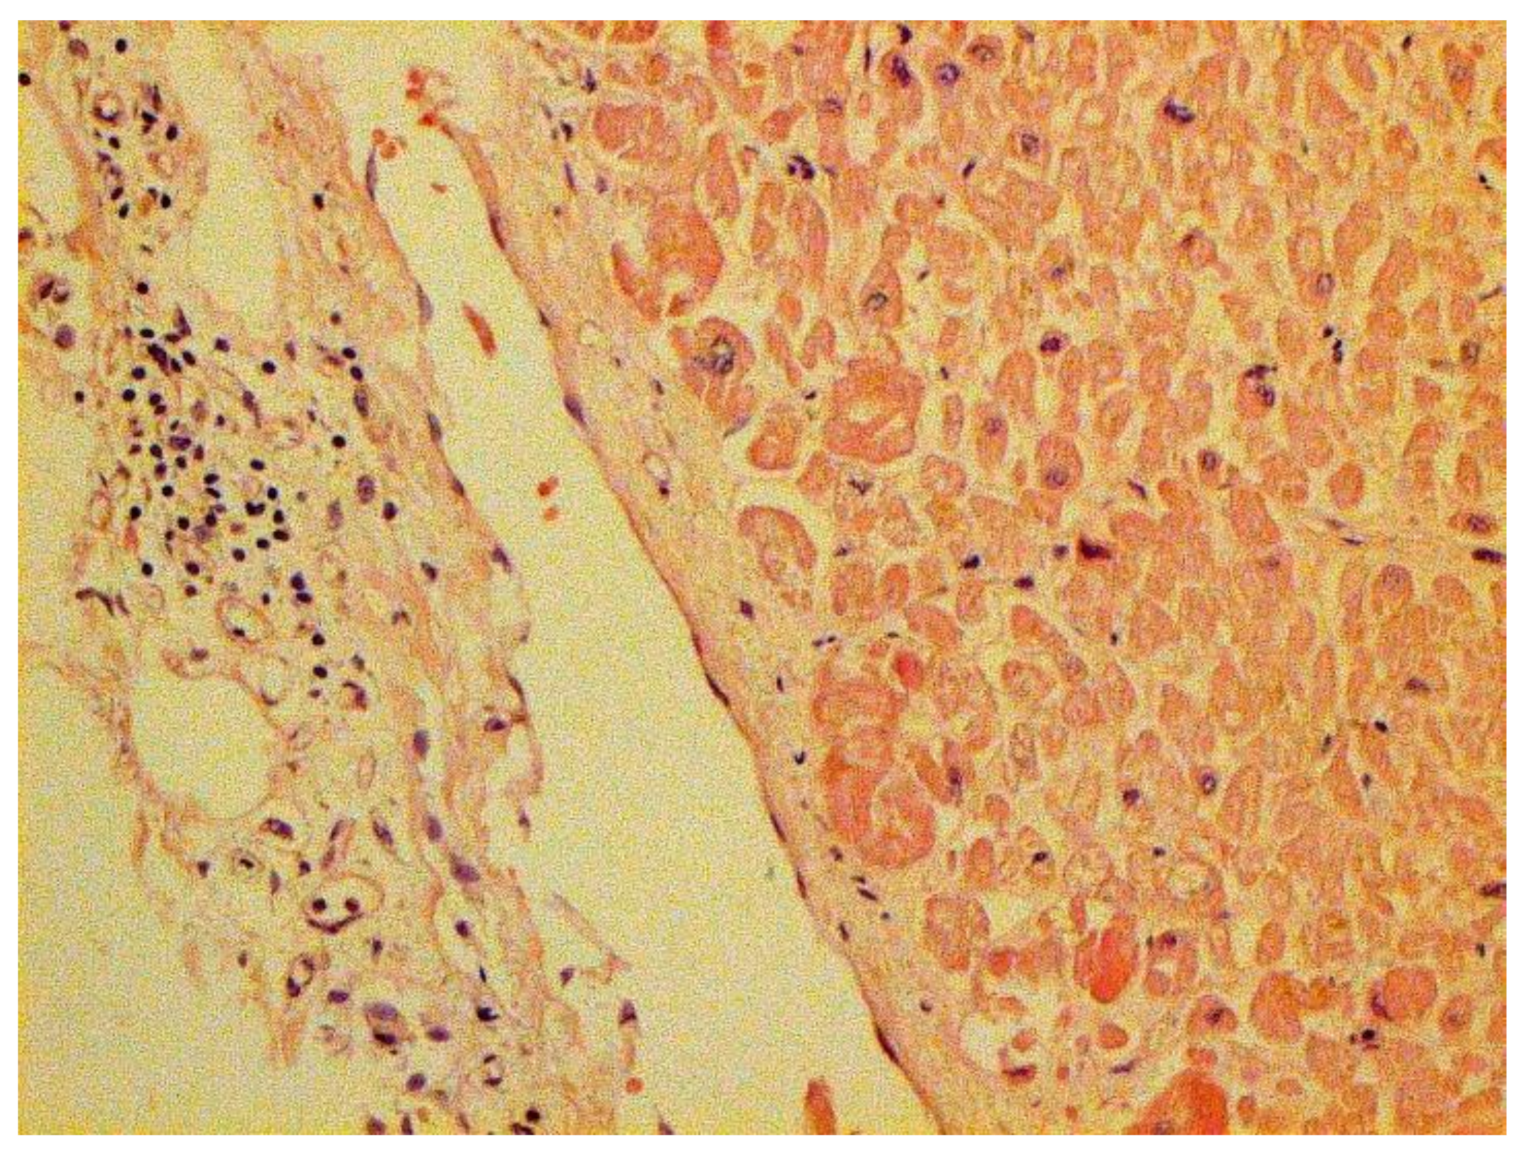

In many vessels, we also observe thrombi in different vessels (Figure 16 and Figure 17). We succeeded in detecting virus spike antigen in endothelial cells as well as in other layers of vascular walls. The formation of fibrin thrombi in blood vessels (probably DIC) and infiltration by T lymphocytes, including cytotoxic cells (Figure 18 and Figure 19), were seen not only in the parenchyma of the organs but in the surrounding tissues as well. It is important to compare the localization of virus antigens and cytotoxic CD8+ cells (Figure 20).

Figure 18.

Infiltration of adrenal by CD3+ lymphocytes. IHC ×100.

Figure 19.

Infiltration of pericardium by CD8+ lymphocytes. IHC ×100.